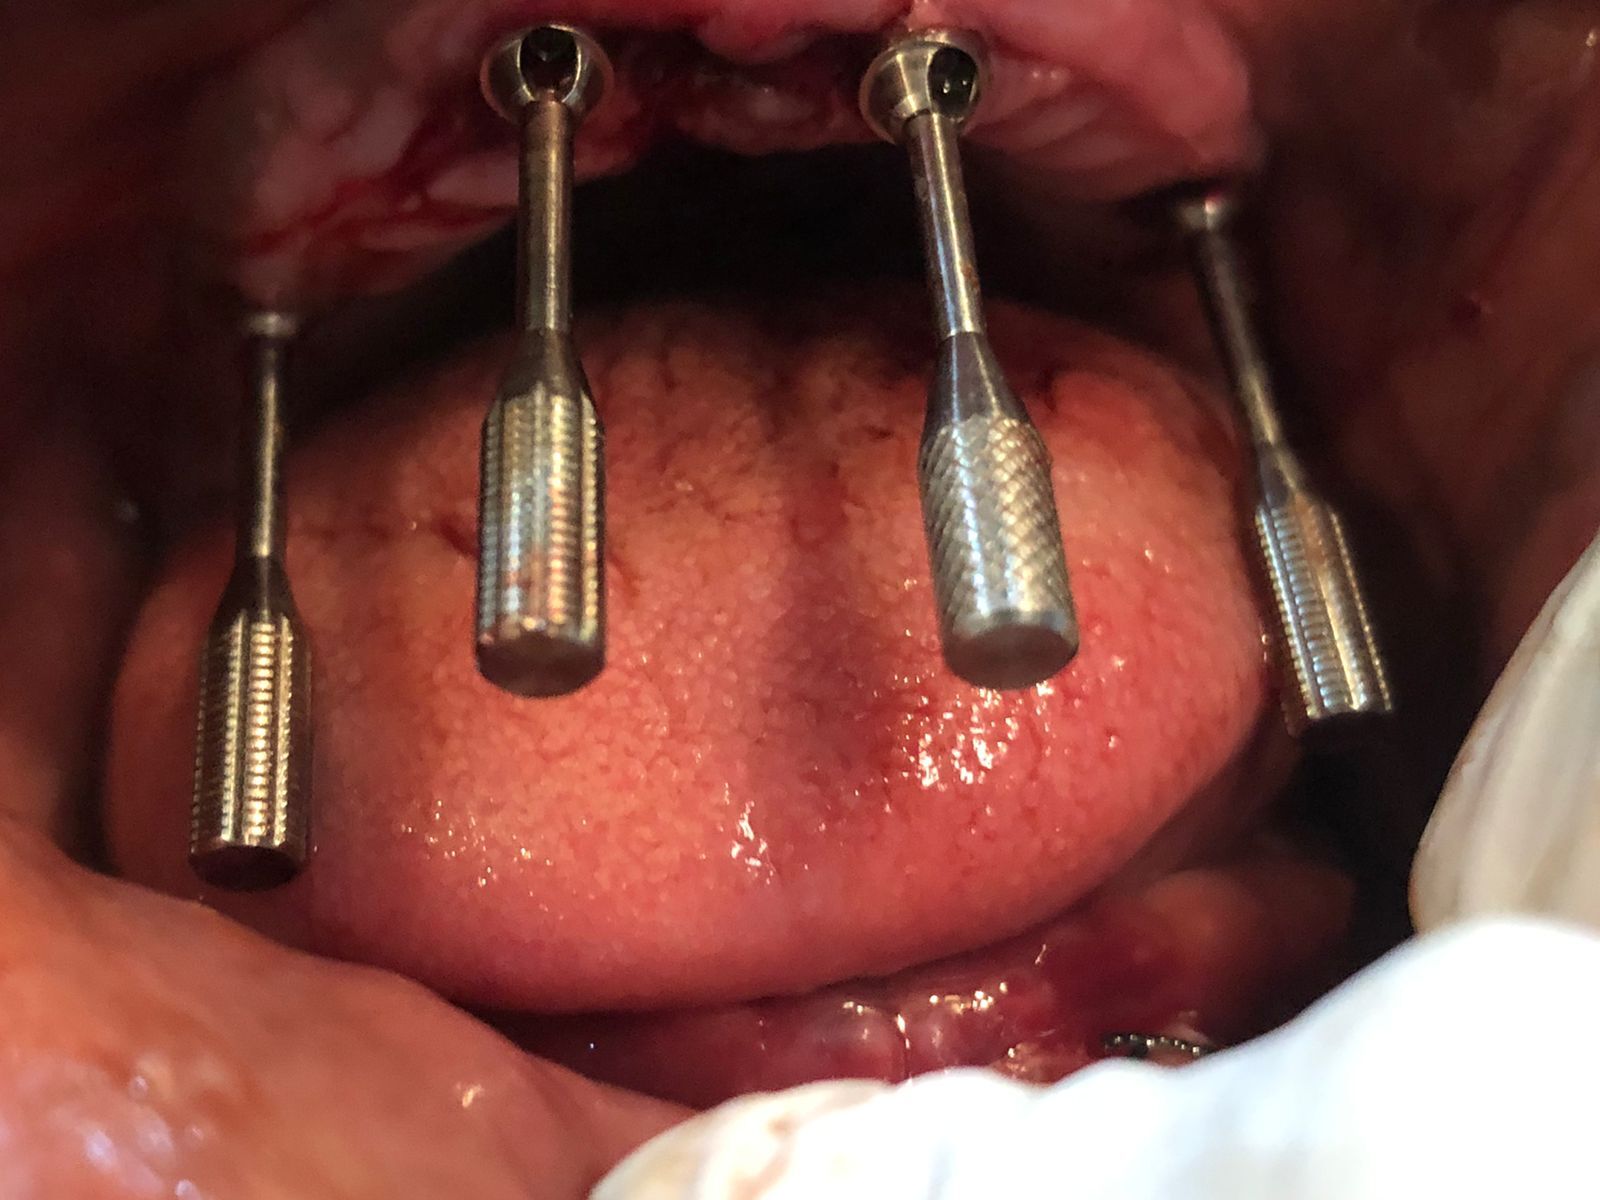

Dental Implants

A dental implant is a root of an artificial tooth. It is fixed into the jawbone and so it can facilitate permanent artificial teeth. Dental implants can support a single artificial tooth or multiple artificial teeth. They are made of dental material like titanium or zirconium. Unlike dentures or other dental restorations like dental bridges, artificial teeth fixed on top of dental implants are closest to natural teeth. They provide superior functionality enabling chewing of food and clear speech. Dental implants are fixed into the jawbone with a dental surgery. Once dental implants are firmly fixed, artificial teeth, dentures, or crowns are placed.

Sinus Lift Surgery

In order to successfully place dental implants you need sufficient bone. In certain situations dentist need to perform specific procedures in order to create bone volume. One such procedure is sinus lift. The maxillary sinuses are empty rooms that have nothing at all in them. When upper teeth are removed, there is often just a thin wall of bone separating the maxillary sinus and the mouth. Dental implants need bone to hold them in place so when the sinus wall is very thin, it is impossible to place dental implants in this bone. There is a solution called a sinus graft or sinus lift graft. The dental implant surgeon enters the sinus and sinus membrane is then lifted upward and donor bone is inserted into the floor of the sinus. After several months of healing, the bone becomes part of the patient’s jaw and dental implants can be inserted and stabilised in this new sinus bone. The sinus graft makes it possible for many patients to have dental implants when years ago there was no other option other than wearing loose denture.